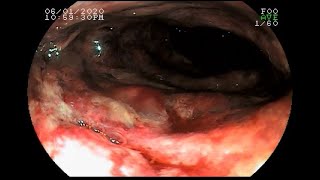

Mesenteric Ischemia

Mesenteric Ischemia Instructional Tutorial Video CanadaQBank.com QBanks for AMC Exams, MCCEE, MCCQE & USMLE URL: http://youtu.be/NTE1caA3sxk.